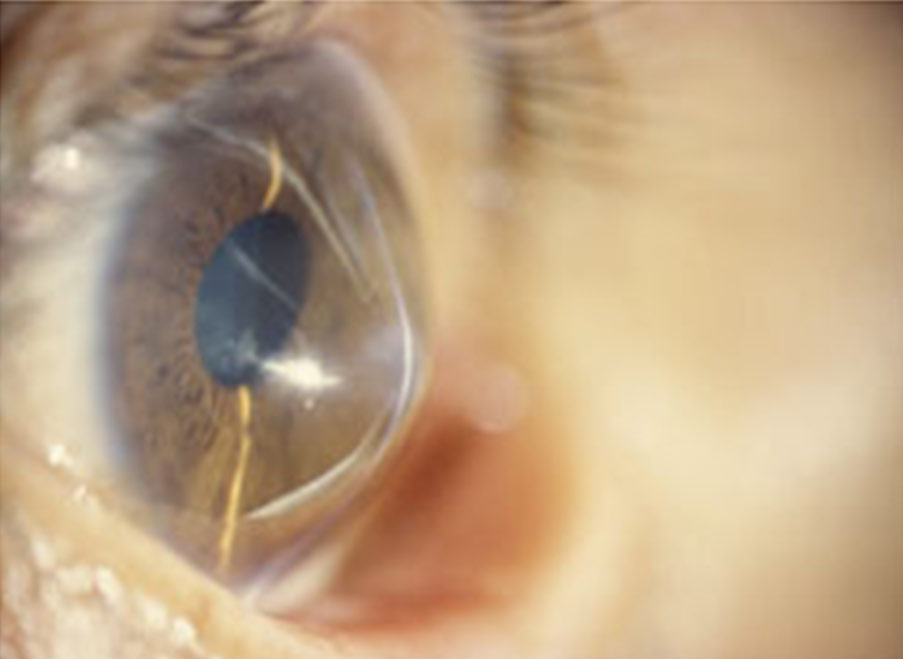

Rizzuti Sign Keratoconus Blurry Vision Keratoconus Glasses or soft contact lenses can correct blurry or distorted vision in early keratoconus. It focuses light into your eye. Keratoconus is when the cornea thins out and bulges like a cone. Changing the shape of the cornea brings light rays out of focus. Keratoconus is a rare eye disorder that occurs when the transparent outer layer of the eye. Blurry Vision Keratoconus.